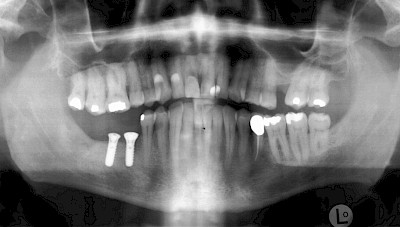

Implantatplanung

Damit Implantate an der richtigen Stelle im Kieferknochen platziert werden könen, gibt es heute vielfältige Möglichkeiten der Planung. In vielen Situationen kann die Erfahrung des Zahnarztes ausreichend sein.

Nicht selten ist jedoch auch eine technisch aufwändigere Vermessung im Vorfeld sinnvoll, z.B.:

- Wenn sich der Kieferknochen abgebaut hat

- Wenn der Nervverlauf im Unterkiefer beachtet werden muss

- Wenn die Ausdehung der Kieferhöhle im Oberkiefer beachtet werden muss

- Wenn wenige Restzähne keine gute Orientierung erlauben

In diesen Fällen kann die Planung mittels verschieden aufwendiger Röntgen-Techniken (Übersichtsaufnahme, DVT) ggf. unter Zuhilfenahme speziell angefertigter Planungsschablonen sinnvoll sein.

Beispiele15 Bilder